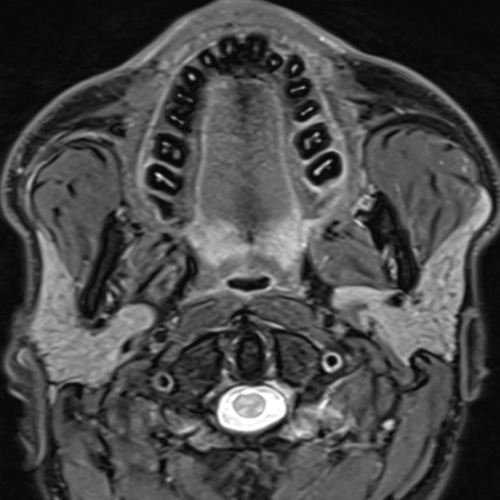

Cet examen est réalisé pour analyser les différentes structures anatomiques ORL : amygdale, langue, cavité orale, glande salivaire, parotide, ganglions

Il est réalisé en cas de douleurs, de suspicion ou d’extension de tumeur ORL, de lithiase.

Cette examen permets de diagnostiquer:

- les adénopathies (ganglions augmentés de taille)

- les infections ORL ( abcès ou phlegmon amygdalien)

- les tumeurs de la parotide

- les masses ou tumeurs ORL ( amygdales, pharynx, larynx)

- les kystes cervicaux (kyste branchial)

- les neurofibromes, paragangliomes